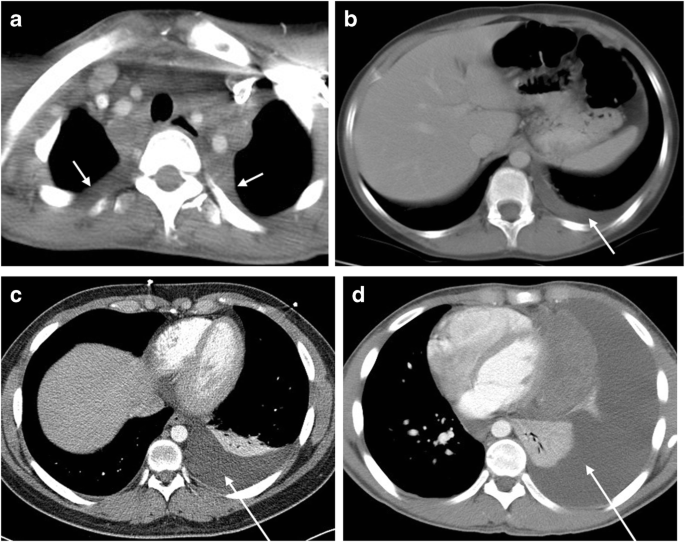

Fig. 2

figure 2

Effusion categories. a Trace effusion (arrows), with at least 1 cm of fluid inferiorly or 1 cm at the apices, as seen here on axial CT image in a 15-year-old girl. The majority of trace effusions were at the apex (129 of 217). This is a distinct finding associated with large mediastinal masses and might reflect transudation from small focal lymphatic channels. b Small effusion (arrow), seen here in an 11-year-old girl on axial CT image, is any effusion 1–3 cm in size. c Moderate effusion (arrow) is any effusion >3 cm in size that reached to mid-thoracic level, as seen in a 16-year-old girl on axial CT image. d Large effusion (arrow), any effusion that extends from the lung base to the apex and displaces heart and mediastinum toward the opposite side, is seen here on axial CT image in a 14-year-old boy